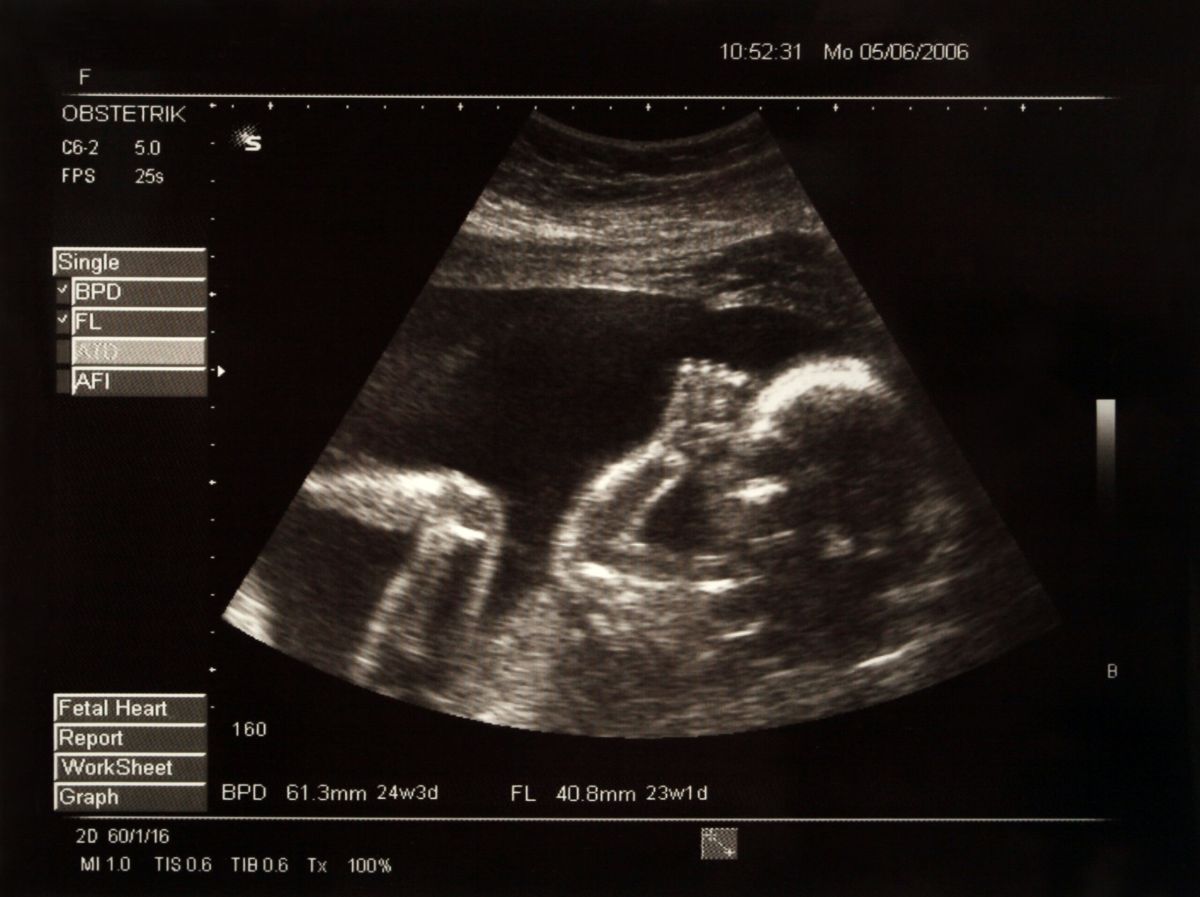

L’anomalie a été découverte lors d’une séance d’ultrasons à la 30e semaine de grossesse. Les parents ont alors décidé de participer à un essai clinique inédit mené conjointement par le Brigham and Women’s Hospital et le Boston Children’s Hospital. Attendre la naissance pour intervenir aurait pu aggraver la malformation et entraîner de graves complications cérébrales. En effet, selon le radiologue Darren Orbach de l’hôpital pour enfants de Boston, 40% des enfants atteints de cette maladie décèdent peu après leur naissance.

L’intervention a été réalisée avec succès en assurant une position optimale du fœtus dans l’utérus de la mère. Des injections ont été administrées pour maintenir l’enfant en place et soulager la douleur. Un cathéter a été utilisé pour ralentir le flux sanguin et réduire la pression. Les chirurgiens ont été guidés par des ultrasons tout au long de l’opération. La petite fille est finalement née deux jours plus tard.